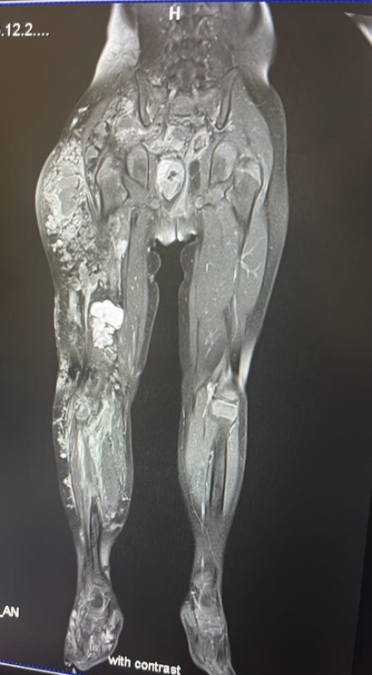

Данный случай считается сложным, так как сосудистая аномалия распространялась из полости малого таза на протяжении всей нижней конечности до стопы. С помощью нового современного МРТ-аппарата специалисты провели МР-исследование малого таза и нижних конечностей за одно сканирование с мультипланарной реконструкцией, также сделали МР-ангиографию с контрастированием.

«Все это врачи сделали за полтора часа, пока ребенок находился в состоянии медикаментозной седации под наблюдением реаниматологов»,- отметил министр здравоохранения Кузбасса.